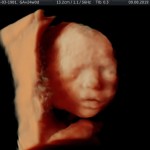

Modalidad de imagen ecográfica que permite evaluar, medir y capturar estructuras fetales superficiales e internas en 3 dimensiones (3D) y también en movimiento y en tiempo real (4D) con programas de realismo aumentado (HD LIVE) e imágenes tomografías fetales (TUI) mejorando significativamente la precisión en las mediciones fetales y la documentaciones de estructuras anatómicas.

Esta tecnología se puede utilizar desde la 6ta a la 40ma semana de embarazo.